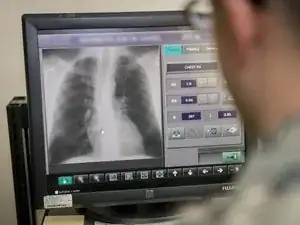

Medical imaging is the process of creating visual representations of the internal structures of the body beneath the skin and bones. These images can then be used for clinical analysis, diagnosis and discovery of abnormalities, and to create plans for medical intervention. Medical imaging uses a variety of technologies based on the area of analysis, including but not limited to “X-ray radiography, magnetic resonance imaging, ultrasound, endoscopy, elastography, tactile imaging, thermography, medical photography, and nuclear medicine functional imaging techniques as positron emission tomography (PET) and single-photon emission computed tomography (SPECT).” (Wikipedia)